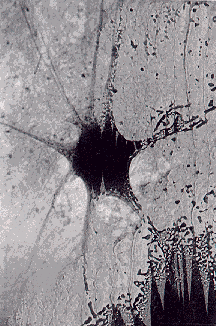

Las neuronas son las células especializadas del Sistema Nervioso . Son las células más especializadas que existen, hasta tal punto que han perdido la capacidad de realizar otras funciones y son incapaces de dividirse, de nutrirse por sí mismas o de defenderse. Por este motivo hay una serie de CÉLULAS ACOMPAÑANTES que nutren, protegen y dan soporte a las neuronas (astrocitos, oligodendrocitos, células de Schwann, etc.).

La forma de las neuronas es muy compleja. Presentan unas prolongaciones más o menos delgadas, denominadas DENDRITAS y, normalmente, otra de mayor tamaño, llamada AXÓN o FIBRA NERVIOSA. Un conjunto de axones o dendritas forman un NERVIO, que suele estar recubierto de tejido conjuntivo. Las dendritas son vías de entrada de los impulsos nerviosos a las neuronas y los axones son vías de salida.